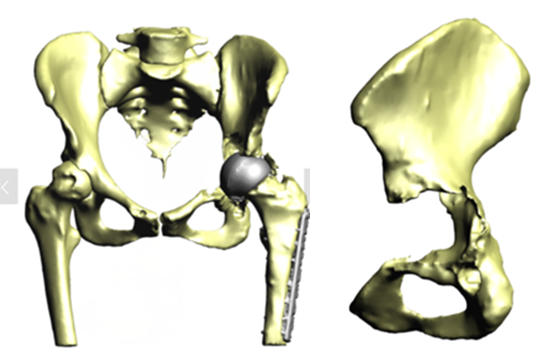

A multidisciplinary team decided that revision surgery was necessary due to the risk of fracture and very high metal ion levels. The plan involved removing the existing MoM implant and fitting a custom 3D-printed acetabular cup. The procedure required meticulous care to avoid causing fractures during implant removal. The new cup would only be effective if the pelvis remained intact.

The operation was successful, with minimal bone loss during implant removal. A custom-made titanium acetabular cup was fitted and stabilized with screws. Postoperative imaging confirmed correct implant positioning and satisfactory fixation. The patient’s recovery was positive, with significant reductions in metal ion levels and the restoration of pain-free hip function.

This case demonstrates the importance of precise surgical planning and execution in complex hip revision surgeries. The use of 3D-printed implants tailored to the patient's anatomy greatly improved the chances of successful fixation despite significant bone loss. Update at 6 years post operative is that the patient living a full and active life with excellent hip function. More details about this type of surgery has been published by Professor Hart: